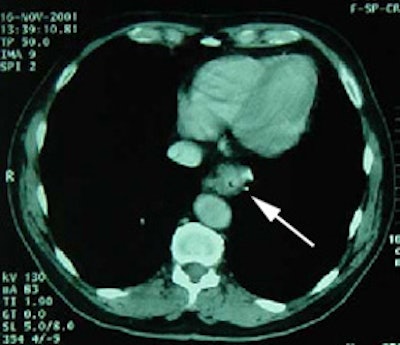

Unsuspected metastatic esophageal carcinoma: The patient shown in the case below was referred for FDG PET imaging for the evaluation of esophageal carcinoma. A CT scan demonstrated abnormal thickening of the distal esophagus (white arrow), but no evidence of metastatic disease. The PET exam revealed long segment abnormal increased tracer activity within the primary esophageal lesion, as well as an unsuspected bone metastasis to the right hip (black arrow). Such findings on PET imaging have tremendous impact on patient management. Case courtesy of CTI.